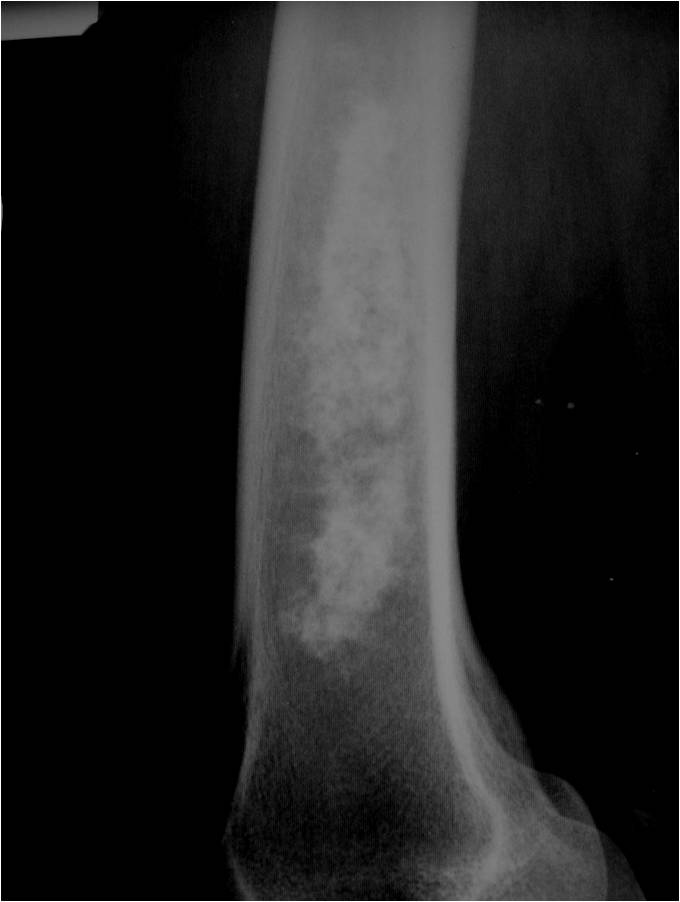

- Localized, radiolucent defect usually with punctate calcifications

- Calcifications are typical but not always present

- Matrix may demonstrate various degrees of calcification

- Calcifications are stippled, punctate, popcorn like calcifications and “Ring and Arc” calcifications

- Cartilage tumors grow in a lobular manner. The perimeters of the lobules undergo

- enchondral ossification that may calcify. If the entire perimeter of the lobule calcifies it appears

- radiographically as a “Ring”. If a portion of the perimeter of a lobule calcifies it forms an “Arc” on

- an X-ray.

- Most commonly found in metaphysis

Plain X-Ray:

- Geographic lytic lesion

- Central often metaphyseal in long bones

- Can be eccentric also

- Expansile remodeling with thinned cortex

- Chondroid matrix with calcifications in majority of tumors

- Approximately 20% have limited or no calcifications

- Endosteal scalloping and cortical expansion is acceptable for phalangeal tumors. In most benign long bone cartilage tumors there is minimal endosteal scalloping but there should be no cortical expansion nor thickening. There should be no cortical destruction and no soft tissue component associated with an enchondroma. Cortical destruction, periosteal thickening, cortical expansion and a soft tissue component indicates a chondrosarcoma of the long bone.